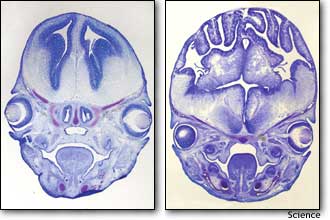

左图是表面平滑、正常的老鼠大脑图,右图则是老鼠被注入经过改造的蛋白质基因之后形成的更大、叠起的大脑图,其看起来很像是人脑图。

结果,老鼠的大脑显著增大,由于头骨容积有限,老鼠的大脑开始像人脑一样叠起,对此,瓦尔什惊讶地表示:“我们没有想到老鼠的大脑会变得这么大,更没有想到会与人脑一样叠起。”事实上,老鼠的大脑通常情况下表面非常平滑,而人脑则布满褶皱并有叠起的现象,因为人脑较大不得不被压挤在头骨里面。